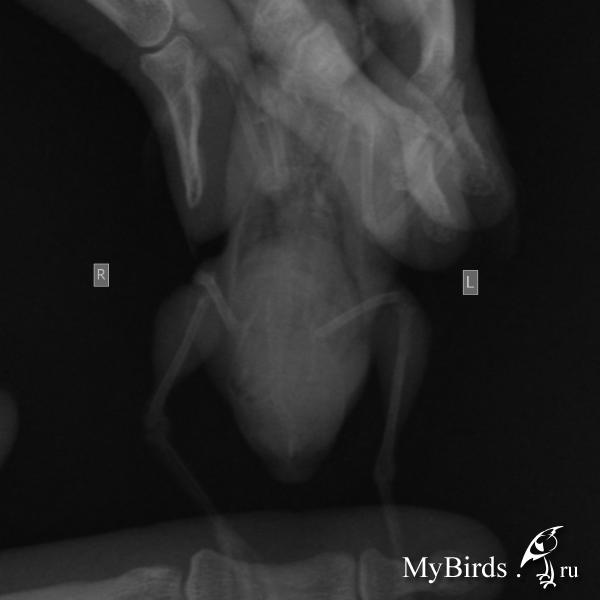

Есть рентген, прилагаю. Очень жду мнения специалиста.

post-42116-1433081614_thumb.jpg

post-42116-1433081628_thumb.jpg

post-42116-1433081652_thumb.jpg

post-42116-1433081673_thumb.jpg

post-42116-1433081688_thumb.jpg

и - срочно - сделать рентген - нужен цифровой, ищите в вет или чел больнице, просите за денги, доза как на хомячка или детскую кисть ребенка, в 2ух проекциях, чтобы разглядеть МЯГКИЕ ткани, снимок выложить на форум- спецы прочтут. (как выложить на форум -см у меня в подписи). Жуть что с животом... ударится не мог? (гематома)

Новообразование вполне может иметь место. тут только пальпация прямая и рентген могут что-то определенное сказать.